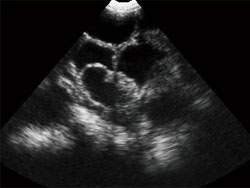

MSU3

Ультразвуковой сканер полного цифрового механического сектора

Feline Canine

галерея